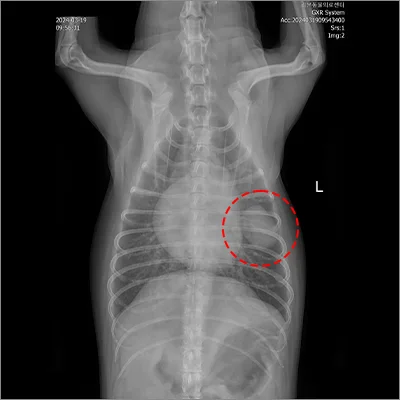

📍 폐엽절제

폐엽절제 전

폐엽절제 후

정확한 진단과 수술로 삶의 질을 회복합니다